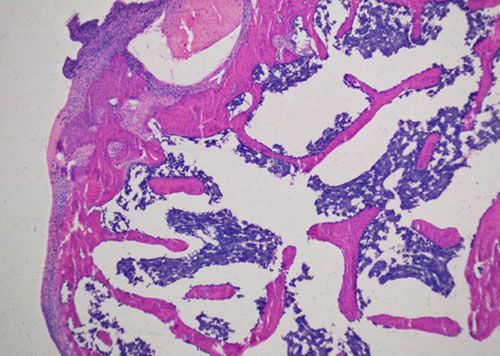

蘇木精-伊紅染色法 ( hematoxylin-eosin staining ),簡稱HE染色法,石蠟切片技術里常用的染色法之一,也可以用于未脫鈣骨硬組織切片。蘇木精染液為堿性,主要使細胞核內的染色質與胞質內的核糖體著紫藍色,伊紅為酸性染料,主要使細胞質和細胞外基質中的成分著紅色。HE染色法是組織學、胚胎學、病理學教學與科研中最基本、使用最廣泛的技術方法。

未脫鈣大鼠股骨HE染色